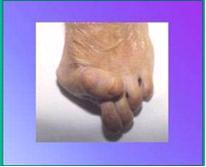

- Griffes d’orteils ou métatarsalgies

- Pathologie du 5e rayon : la bunionette

Un traitement chirurgical s’avère nécessaire quand la déformation devient trop douloureuse et que la personne rencontre de plus en plus de difficultés pour se chausser et marcher. L’idéal est de ne pas attendre que les autres rayons soient atteints par la déformation (orteils en griffes, douleurs plantaires) car dans ce cas, l’intervention sera plus lourde puisqu’elle portera sur l’ensemble de l’avant pied.